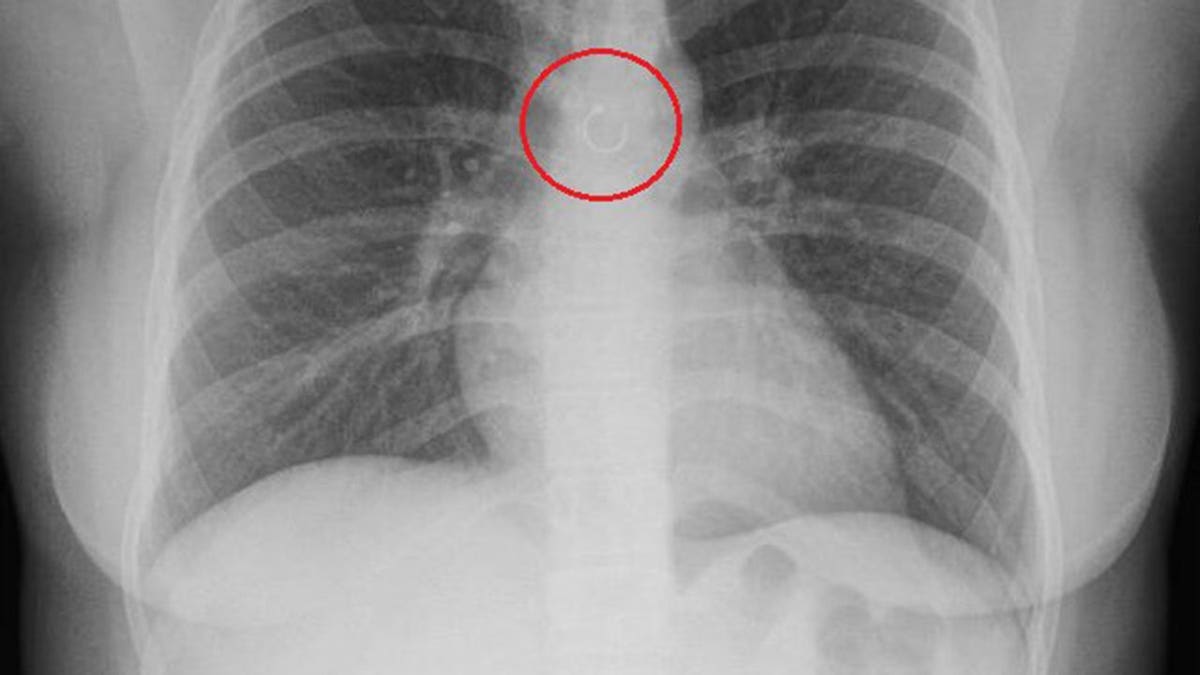

A TikToker in Mexico thought her cough that wouldn’t go away was just a reaction to the changing weather. Instead, it was her own nose ring, lodged deep within her lungs.

In videos, she shared that the stray accessory sat a mere 0.5 millimeters from her aorta, Jam Press reported.

If the metal had punctured her lung or heart before doctors discovered it, Deyanira said she likely would have died from a lung collapse or perforated aorta.